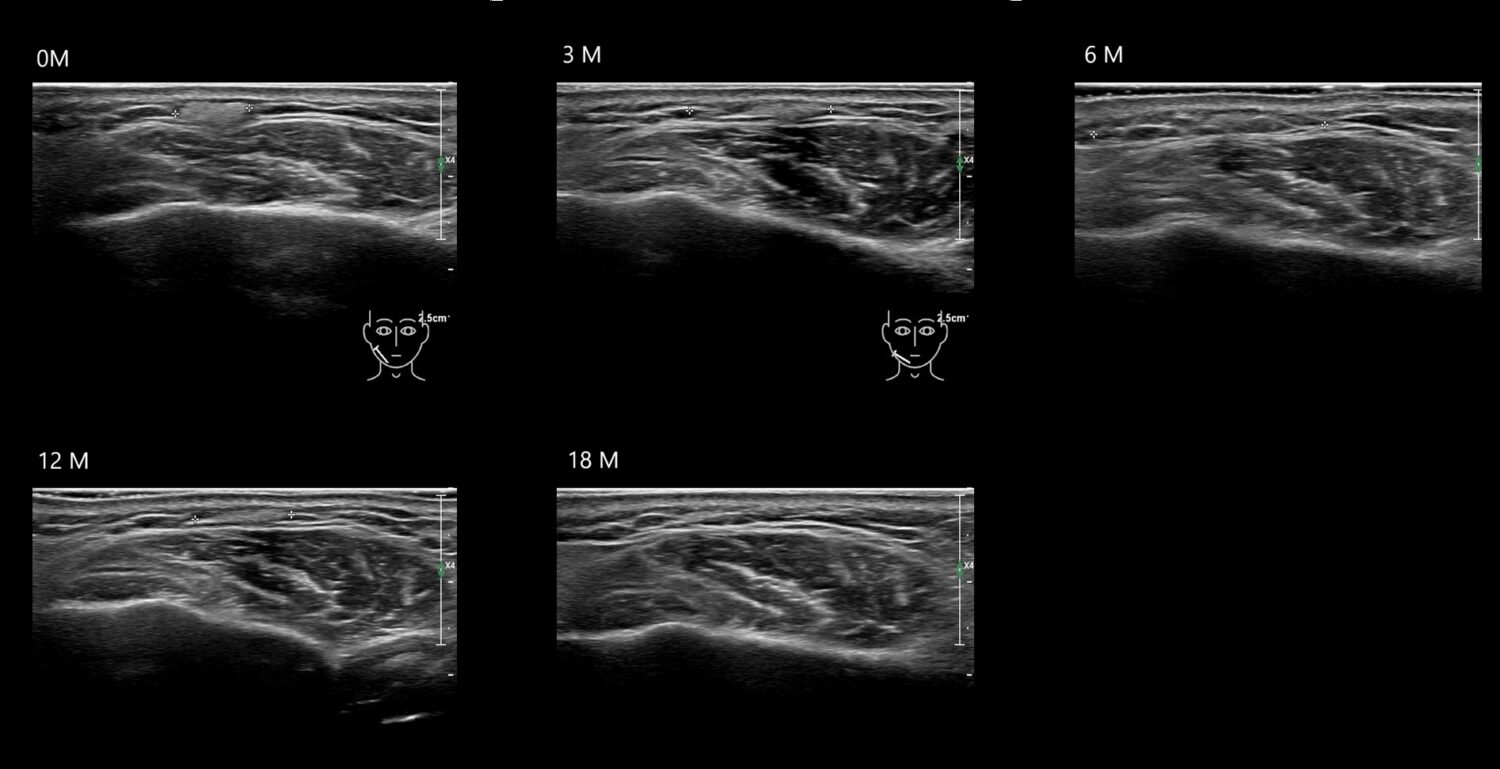

HAca14e